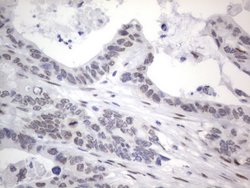

RBFOX1 Mouse anti-Human, Clone: OTI4F9, lyophilized, TrueMAB™

| Immunohistochemistry (Paraffin), Western Blot | |